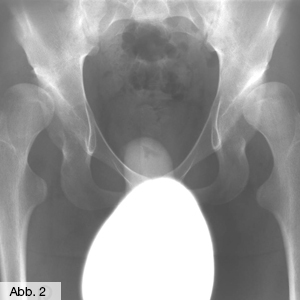

Die Hüftdysplasie ist eine häufiger vorkommende Fehlbildung bei Kindern, die überwiegend bei Mädchen festgestellt wird und unter anderem aufgrund einer Beckenendlage des Kindes verursacht werden kann. Es handelt sich dabei um eine mangelnde Ausbildung der Hüftpfanne, die, wenn sie unbehandelt bleibt, später zu einem vorzeitigen Verschleiß der Hüfte (Dysplasiecoxarthrose) bis hin zu Verrenkungen, Hinken oder schmerzhaften Gangstörungen führen kann. Neben bestimmten Untersuchungsbefunden (z.B. Asymmetrie der Gesäßfalten, Beinverkürzung) kann die Erkrankung durch eine Ultraschalluntersuchung festgestellt werden. In Deutschland ist heute eine routinemäßige Ultraschalluntersuchung (Sonographie, Abb. 2) im Rahmen der U3 (6 Wochen) meist bei Kinderärzten vorgesehen. Es ist aber sehr zu empfehlen, eine erste Ultraschalluntersuchung bereits bei der Geburt durchzuführen, um eine evtl. notwendige Behandlung sofort zu beginnen. In unserer Klinik für Orthopädie bieten wir das gesamte Spektrum konservativer und operativer Therapiemethoden zur Behebung der Hüftfehlstellung an, einschließlich sonographischer Kontrollen. Sofern die Fehlbildung bei einem Kind frühzeitig diagnostiziert wird, verwenden wir zur Behandlung Spreizhosen oder Bandagen, in Ausnahmefällen kann für einige Wochen auch ein Gips verordnet werden. Führen diese Maßnahmen nicht zum gewünschten Erfolg, muss das Hüftgelenk durch eine Operation in die richtige Position und Form gebracht werden.